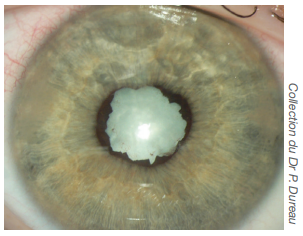

• Accolements entre l’iris et le cristallin appelés synéchies, qui lorsqu’elles sont présentes sur 360°, augmentent le risque d'hypertonie oculaire et de glaucome.

• Cataracte, qui peut être favorisée par l'inflammation chronique mais aussi par la corticothérapie locale surtout, ou générale (orale ou intraveineuse).

Synéchies irido-cristalliniennes